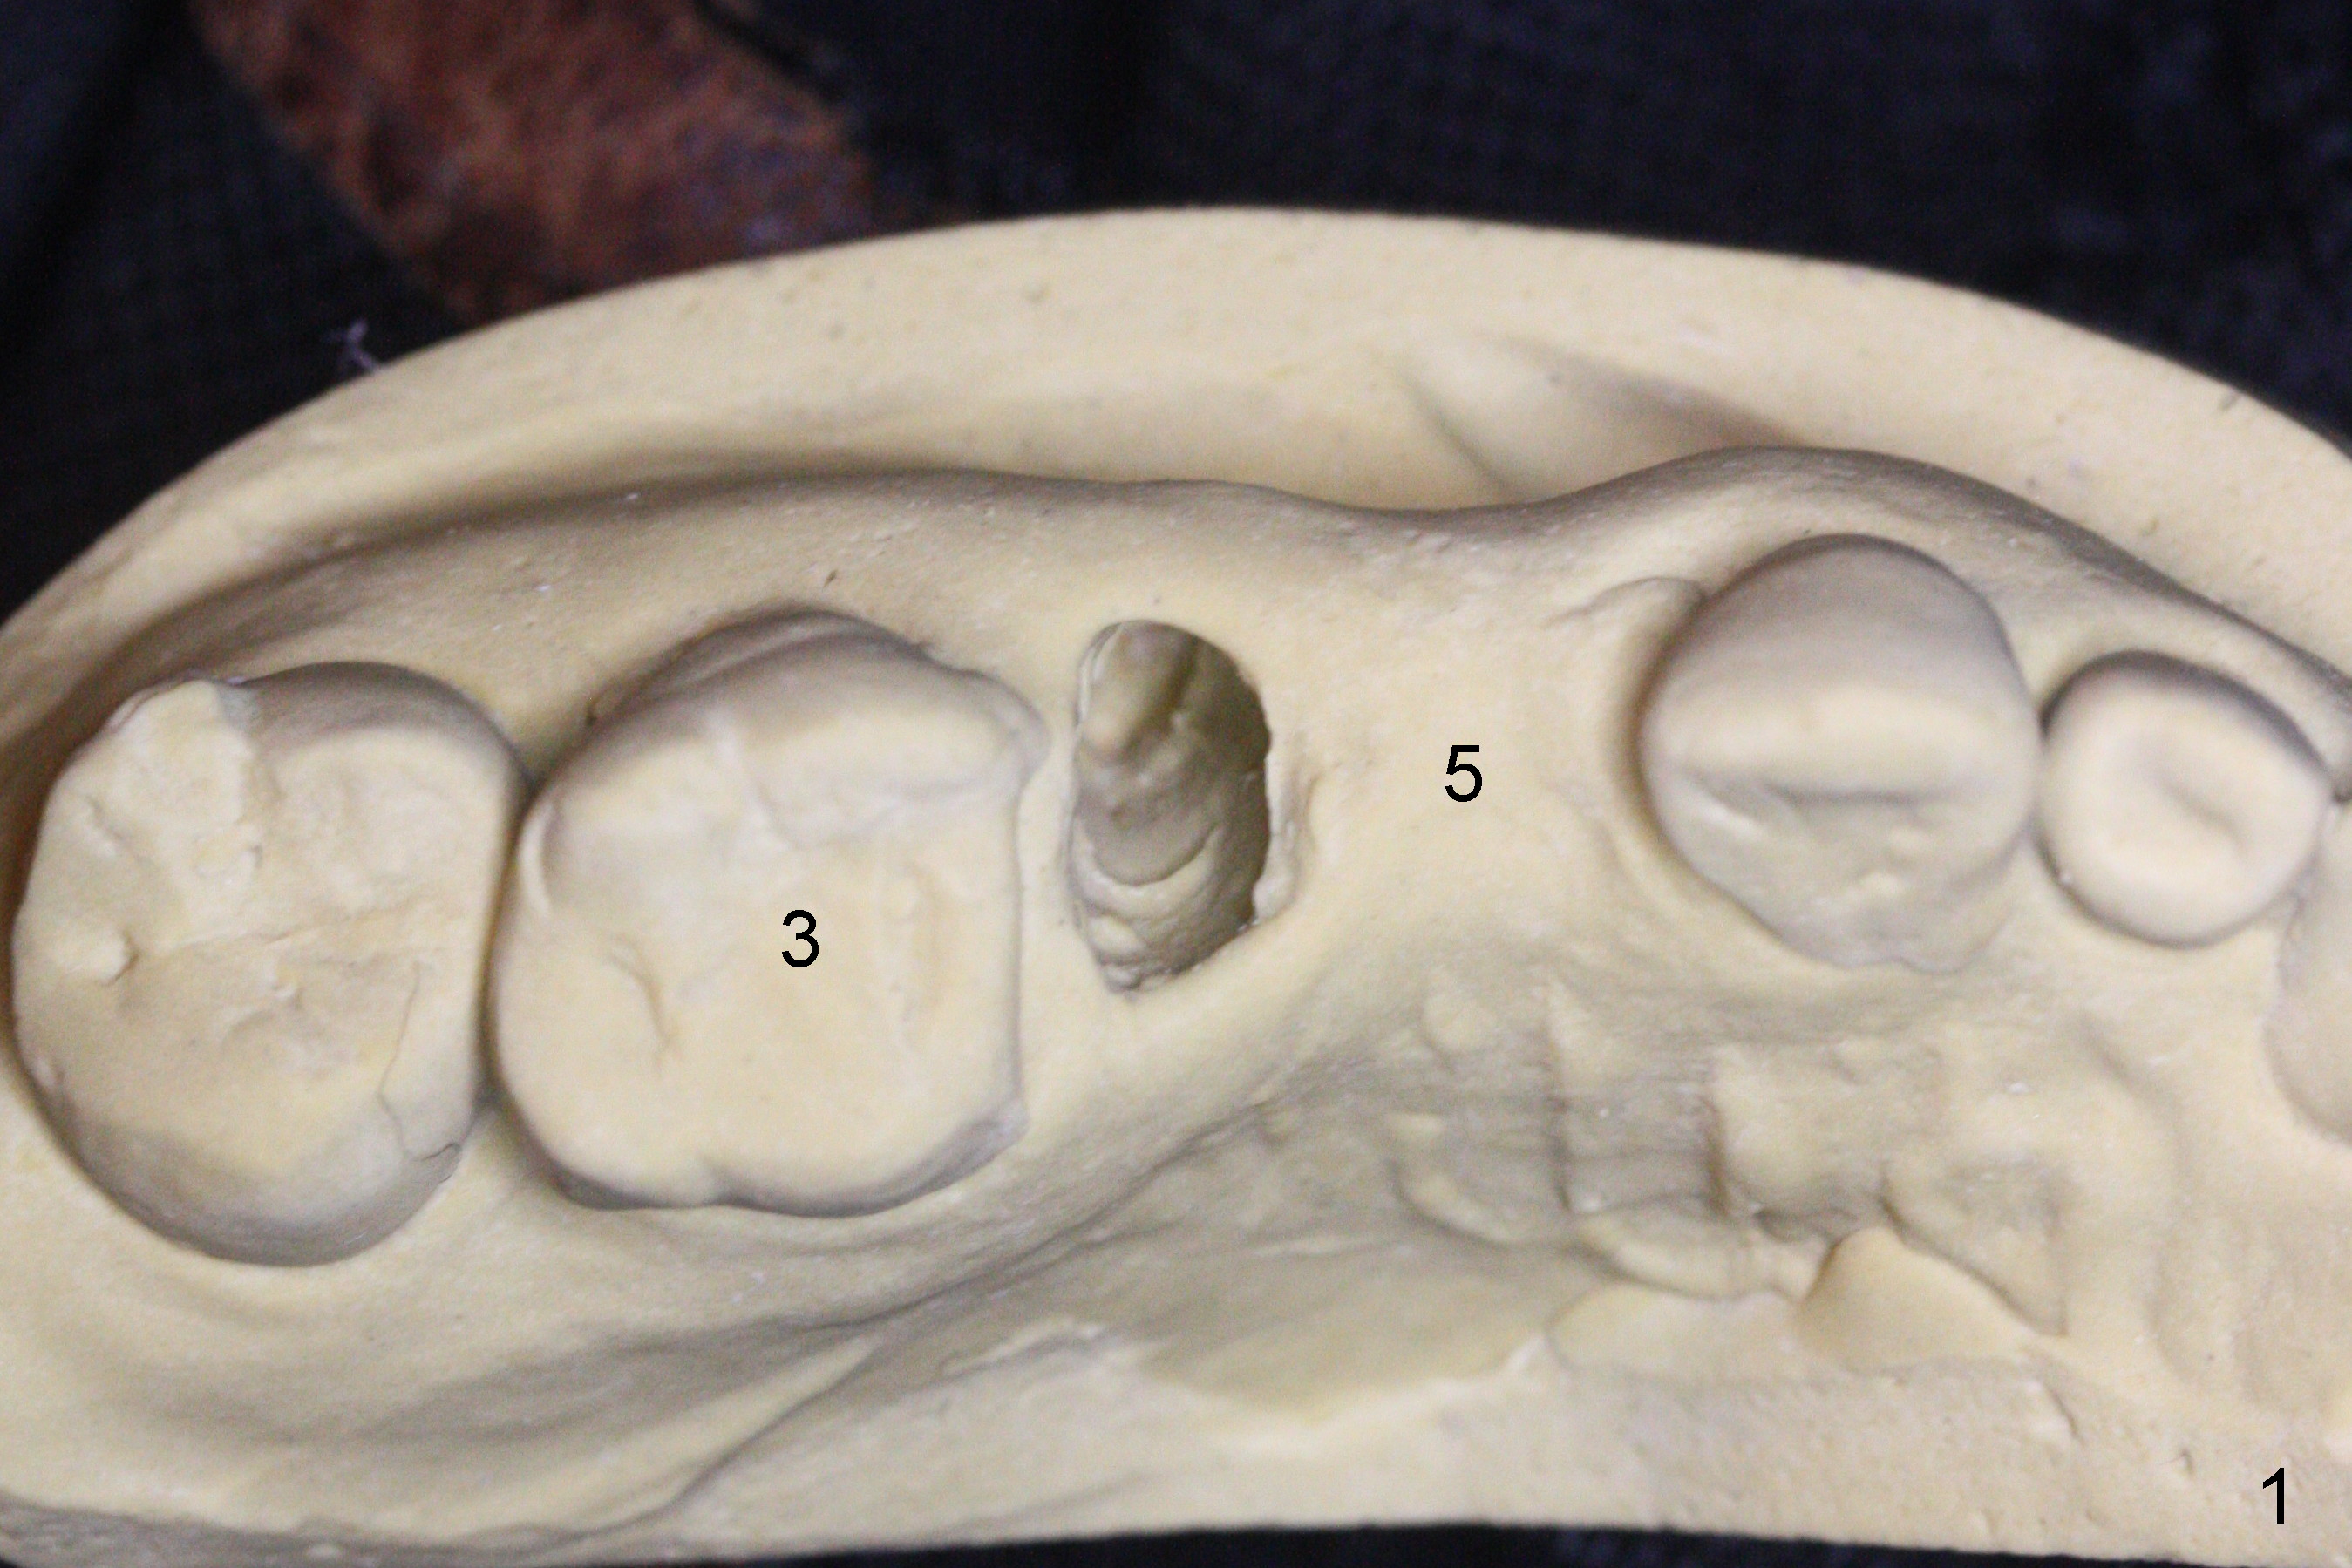

The buccal plate of the socket of #4 is thin and short (Fig.1, 5B (coronal section of the socket) red area) with apical perforation (Fig.5B >). Osteotomy at #4 starts with 1.6 mm drill in the palatal slope (Fig.2 circle; Fig.5C blue arrow), while that at #5 with Magic Split (Fig.2 black line). In fact sinus perforation occurs with the 1.6 mm drill. Osteotomy increases by using Magic Drills sequentially (2.8 and 3.3 mm) at #4 and Magic expander (3.0 mm) and the same Magic Drills at #5 (Fig.3). A 4x11 mm dummy IBS implant is placed with insertion torque of 45 Ncm at #4 with apparently intruding into the sinus (Fig.3). When a 4.5x9 mm implant is placed, the insertion torque is actually reduced (<35 Ncm, Fig.4). As osteotomy or implant diameter enlarges, it shifts buccally with less bone contact buccally (Fig.5D, as compared to Fig.5C)). In brief, once a dummy implant has achieved a reasonably high stability, do not over seat it. A small immediate implant may have more solid bone contact.